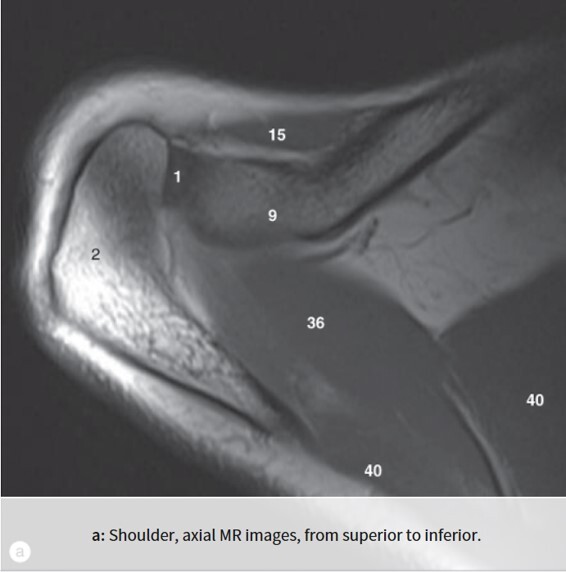

1

Q

Label 1,2,9,15,36,40

A

1=Rt. AC joint

2=Rt. Acromion of scapula

9=Rt. Clavicle (acromial end)

15=Rt. deltoid muscle

36-Rt. supraspinatous muscle

40=Rt. trapezius muscle